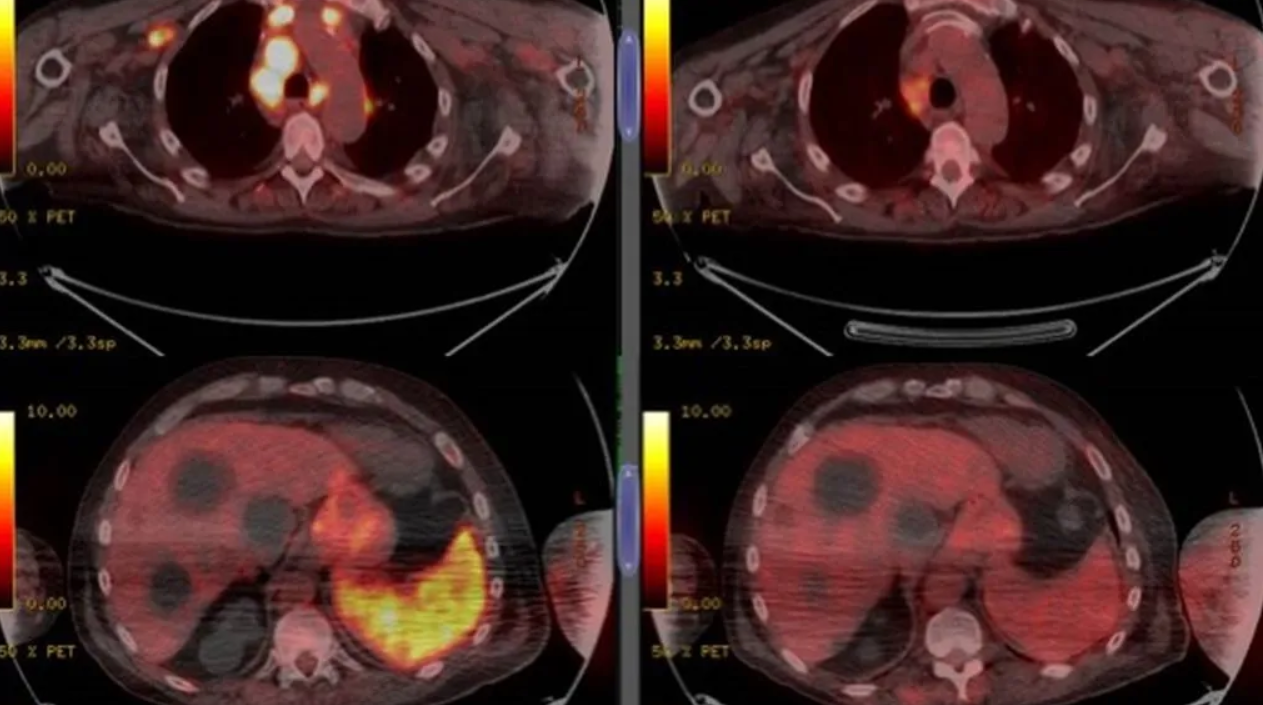

Cuatro meses después, un examen reveló una disminución generalizada del linfoma.